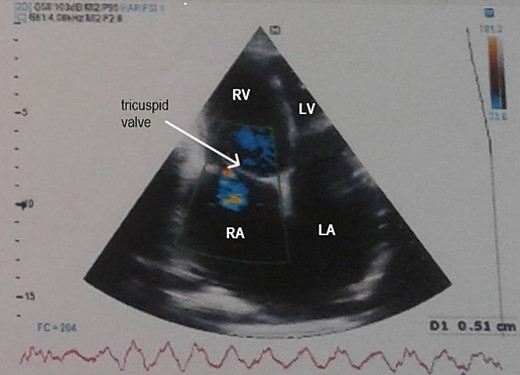

Electrocardiogram (Fig. 1) showed an atrial fibrillation at 120 c/mn with normal axis and a T wave inversion in anterior. Chest radiography (Fig. 2) revealed pericardial calcifications and a mild cardiomegaly. Transthoracic echocardiography (Figs 3–5) showed a pericardial thickening, an important distension of left atrium (LA diameter = 66 mm, LA surface = 33 cm2) and the inferior vena cava (23.7 mm), a calcified mitral leaflets as well as the subvalvular apparatus, restriction of the posterior mitral leaflet with moderate mitral regurgitation (Pisa: 6 mm and ERO: 35 cm2), dilated right heart cavities with moderate tricuspid regurgitation and severe pulmonary hypertension (62 mmHg), preserved left ventricular systolic function (EF LV: 63%) with paradoxical septum. The patient was on lasilix 40 mg one tablet per day, aldactone 50 mg one tablet per day and digoxin 0.25 mg one tablet per day.

Transthoracic echocardiography showed pericardial thickening, moderate tricuspid regurgitation and biatrial dilation. RA: right atrium, RV: right ventricle, LA: left atrium, LV: left ventricle.

Transthoracic echocardiography showed moderate mitral regurgitation. RA: right atrium, RV: right ventricle, LA: left atrium, LV: left ventricle.